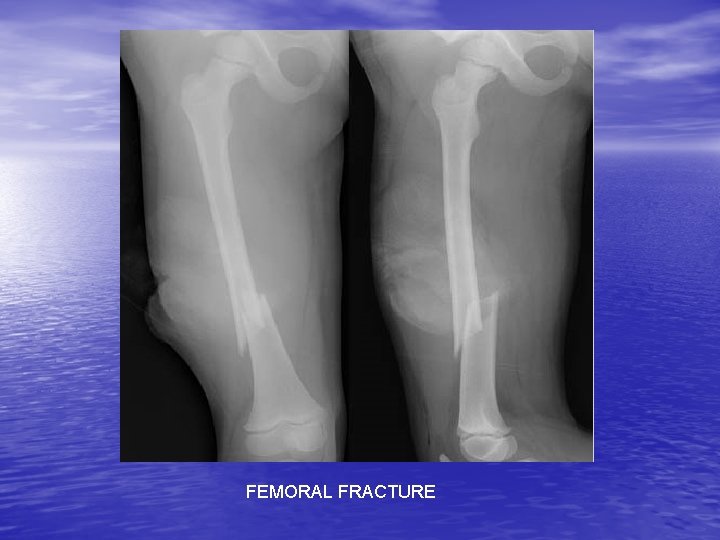

FEMORAL FRACTURE

FEMORAL STRESS FRACTURE